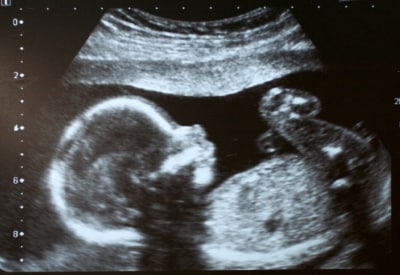

Ultrasound is effectively a high-frequency sonar system, measuring the minute echoes of sound waves as they pass through the body. Ultrasound images (see Figure 8) resemble x-rays except that they are displayed in real-time.